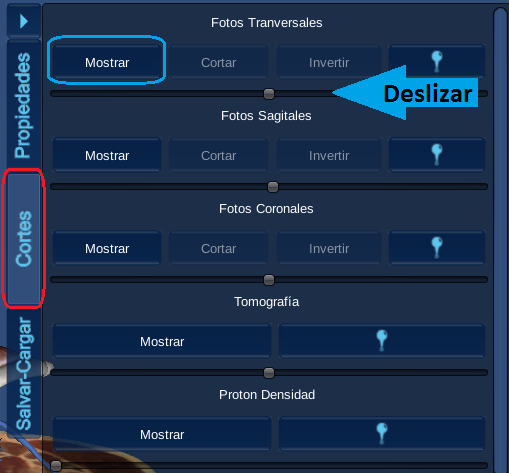

1.Seleccione la pestaña de corte

2.Seleccione el plano de

fotografía en el que desee realizar el corte (Transversal, sagital y/o coronal) , haga clic en el botón mostrar.

4. Haga clic en el botón cortar de la pestaña de cortes